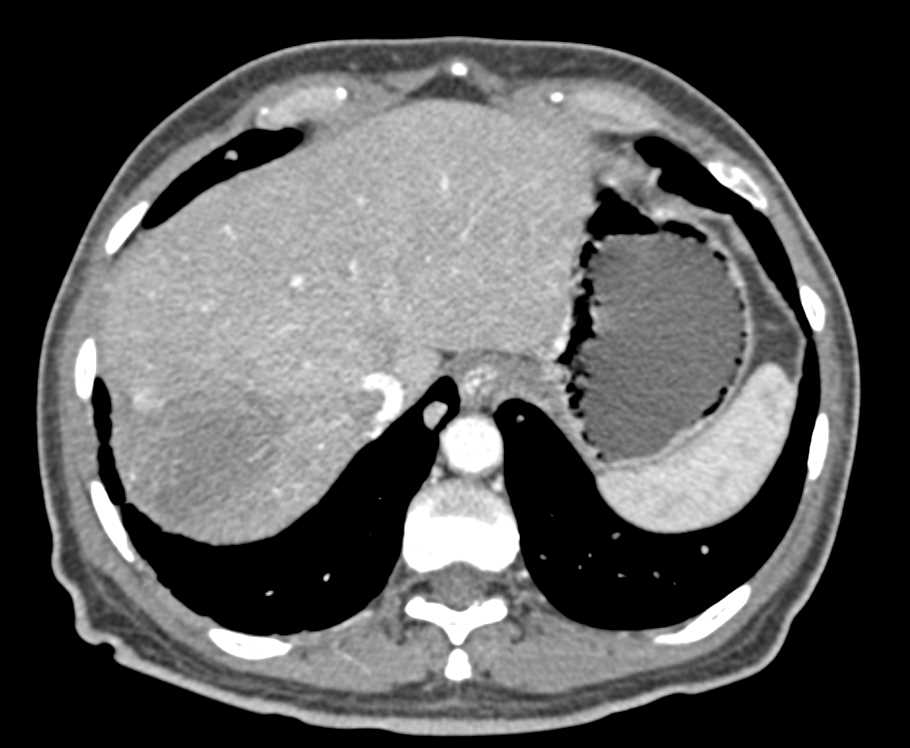

Acute Pyelonephritis Bilaterally